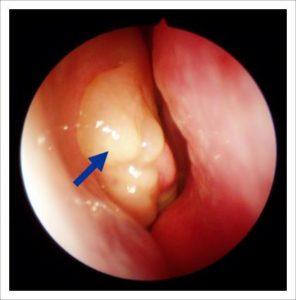

- образуются фолликулы в горле, гнойный налет, пробки;